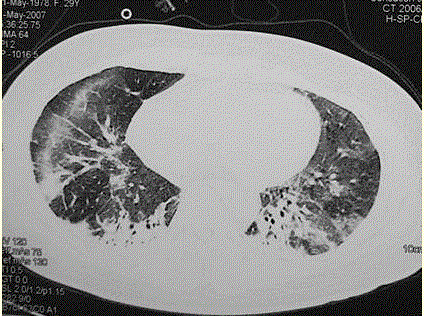

问题 患者女,29岁。间断干咳10年余,加重4个月,伴进行性呼吸困难1个月。病程中出现双手及双足非凹陷性肿胀、双侧膝关节及双侧肘关节对称性肿痛,面部出现细小红色丘疹。体检:T 36.5℃,P 88次/min,R 22次/min,BP 110/75 mmHg,SpO 93%(自然)。额部、前胸及后背散在红色小丘疹,双肺呼吸音增强,双肺中下肺野可闻及爆裂音,右肺明显。胸部CT 如图所示。 下一步的处理措施包括(提示 肺泡灌洗液细胞分类:巨噬细胞41%,淋巴细胞58% ,分叶核细胞1%,经皮肺活检为NSIP富细胞型。)

选项 A.病理诊断已经明确,直接治疗 B.开胸肺活检 C.皮肤活检 D.检测抗核抗体 E.检测肌酶谱 F.皮肤活检 G.J0-1抗体 H.痰找瘤细胞

答案 CDEFG